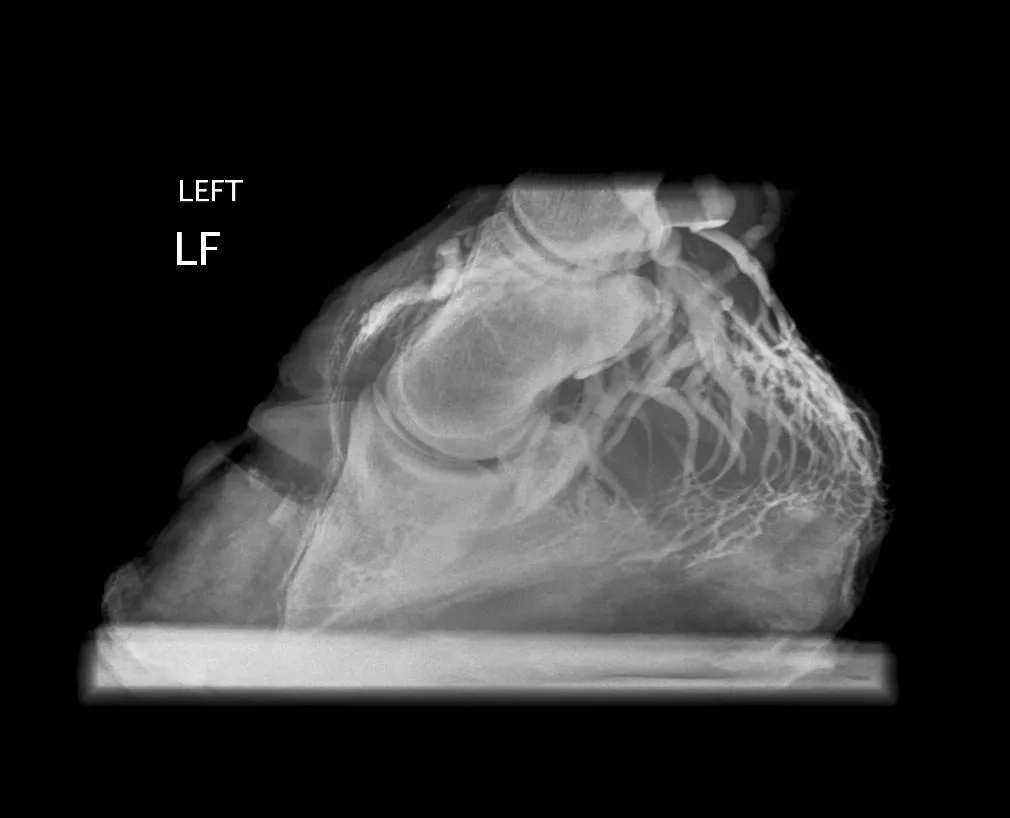

venogram

An image of venogram (an x-ray test that involves injecting x-ray contrast material [dye] into a vein to shows how blood flows through your veins).